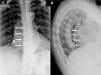

Anteroposterior (A) and lateral (B) radiographs of thoracic spine showing the bone bridges in right anterolateral aspect of 4 contiguous vertebral bodies (white arrows) consistent with the diagnosis of diffuse idiopathic skeletal hyperostosis (DISH). The lateral radiograph also reveals that these bone bridges form angles of more than 45° with the vertebral border.

A 67-year-old woman presented with a 5-year history of mechanical thoracolumbar pain that responded satisfactorily to nonsteroidal anti-inflammatory agents. She had intermittent inflammatory low back pain since the age of 25 years, and 2 episodes of acute anterior uveitis at 30 and 32 years of age, respectively. She had 2 siblings who had been diagnosed as having human lymphocyte antigen (HLA)-B27-positive ankylosing spondylitis (AS). Physical examination revealed limited axial mobility (modified Schöber test: 2.5cm) and chest expansion (2cm), and bilateral positive sacroiliac maneuvers. The results of her analyses were normal (erythrocyte sedimentation rate 16mm/h; C-reactive protein 2.6mg/dL) and she was HLA-B27-positive. Thoracic spine radiographs showed bone bridges on right anterolateral aspect of 4 contiguous vertebrae (Fig. 1) compatible with Forestier-Rotés-Quérol disease, or diffuse idiopathic skeletal hyperostosis (DISH), and, in pelvis, bilateral grade 3 sacroiliitis (Fig. 2A). Computed tomography (CT) of the sacroiliac joints revealed sclerosis and erosions (Fig. 2B and C), confirming the coexistence of AS and DISH.